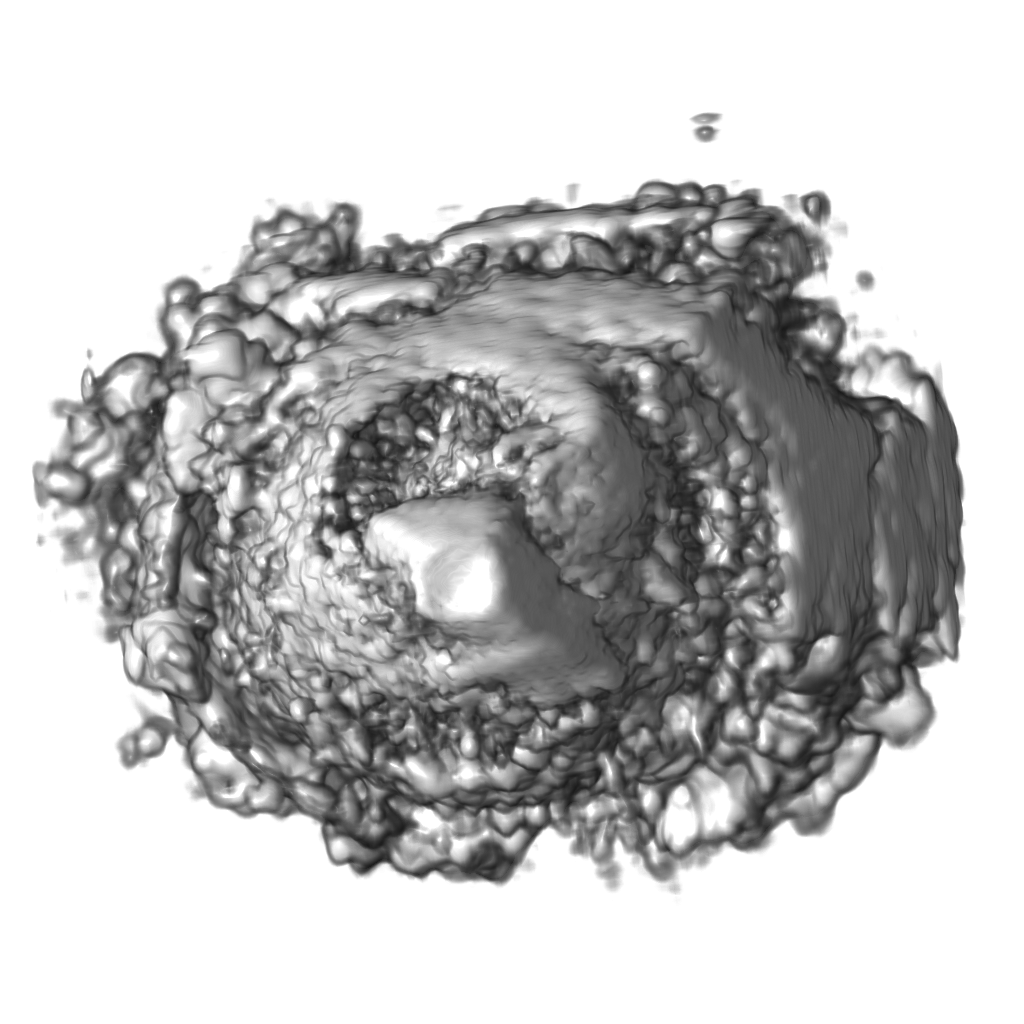

Recent works show that global illumination models based on gradient-free methods are suitable for rendering ultrasound volumes Ropinski10 ; solteszova10 . Ropinski et al. described a volumetric lighting model which simulates scattering and shadowing Ropinski10 . They use slice-based volume rendering from the view of the light source to calculate a light volume and raycasting to render the final image (see Figure 7b). A perceptual evaluation of the generated images indicates, that the proposed model yields stronger depth cues than gradient-based shading. Šoltészová et al. presented a single-pass method for simulation of light scattering in volumes solteszova10 . Light transport is approximated using a tilted cone-shaped function which leaves elliptic footprints in the opacity buffer during slice-based volume rendering. They use a slice-based renderer with an additional opacity buffer. This buffer is incrementally blurred with an elliptical kernel, and the algorithm generates a high-quality soft-shadowing effect (see Figure 7c). The light position and direction can be interactively modified. While these two techniques have been explicitly applied to 3D US data, the application of other volumetric illumination models potentially also improves the visual interpretation of 3D US data. Figure 8 shows a comparison of six different shading techniques as applied to a 3D US scan of a human heart. While the first row of Figure 8 shows examples for the already addressed shading techniques, the second row shows three alternative approaches. Figure 8d incorporates scattering of light in volume data, as proposed by Kniss et al. kniss02halfangle . Their slicing technique allows textured slices to be rendered from both light and viewing direction simultaneously. By sampling the incident light from multiple directions while updating the light’s attenuation map, they account for scattering effects in slice-based volume rendering. Figure 8e shows the application of the directional occlusion shading technique schott09directionalocclusion . This technique constrain the light source position to coincide with the view point. Finally, Figure 8f shows the application of a technique based on spherical harmonic lighting lindemann10materials .